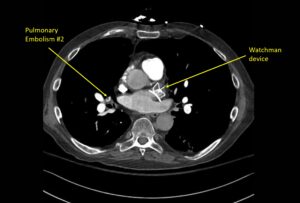

Wolff A, et al. Right atrial thrombosis. CT axial, PE 2

Wolff A et al. Right atrial thrombosis. CT axial PE 2